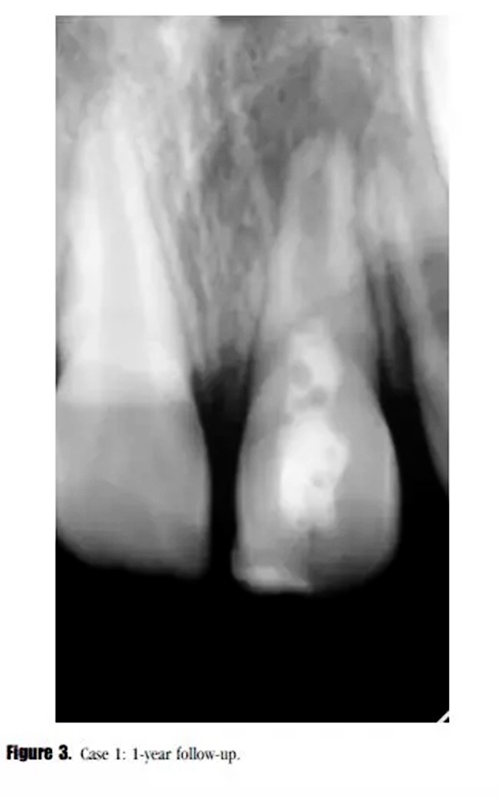

在第12個(gè)月的評(píng)估中,叩診與捫診又輕微不適。在臨床牙冠上未發(fā)現(xiàn)充填材料與牙體的縫隙以及隱裂線,探診深度正常。我們采用了一種細(xì)菌加強(qiáng)型封閉劑來預(yù)防再感染。影像學(xué)評(píng)估顯示,根尖周投射影增大、牙根停止發(fā)育,以及近中根管內(nèi)壁的輕微吸收。(圖3)